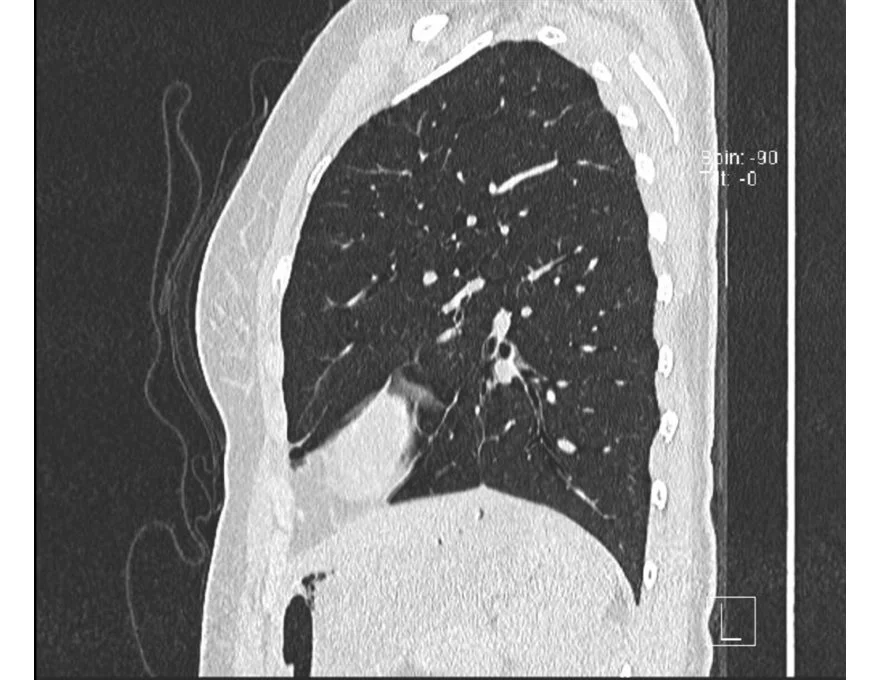

All the lung images are from a AATD patient

• Alpha-1 Antitrypsin Deficiency (AATD) is an inherited genetic disease of European origin characterized by an increased risk of illness in the lungs and liver, among other organs. Additionally, it is distinguished by a low percentage of the AAT protein that acts as an anti-inflammatory and protection source for the lungs. This protein is produced in the liver, and the liver of the patients does not release the protein due to low production levels. Consequently, as the protein accumulates, liver damage develops. People with AATD can suffer from chronic obstructive pulmonary emphysema (COPD), cirrhosis, and other medical issues.

To date, there is no known cure for the disease, but there are treatments that help reduce lung damage, such as respiratory therapy, lung and liver transplantation, and augmentation therapy. Patients take this treatment throughout their lives which consists of receiving a weekly dose of AAT protein intravenously to help the lungs. However, there is currently no treatment for liver damage.